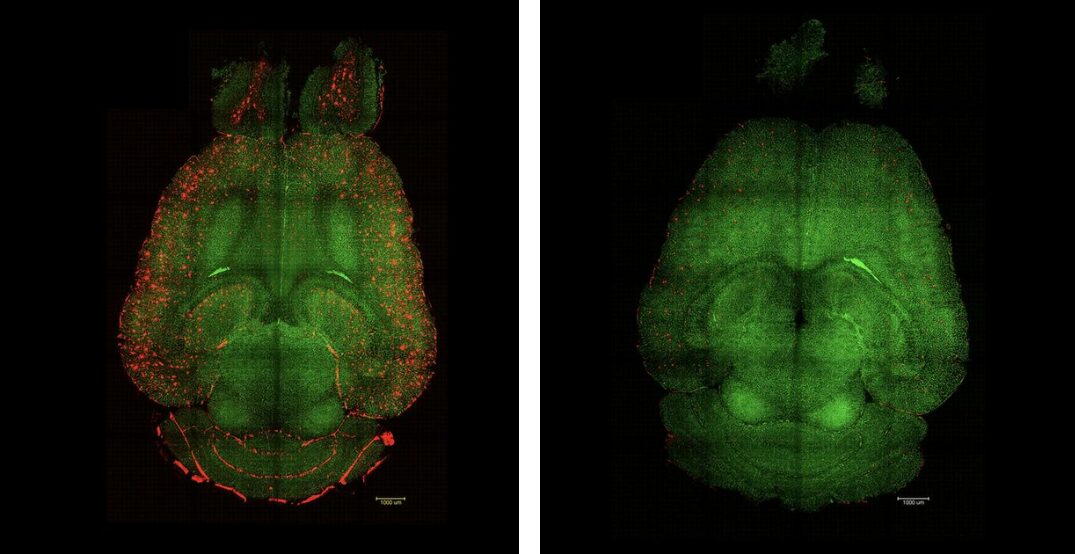

Left-hand image:  Light sheet fluorescence microscope images of mouse brain 12h after NOT being treated with nanoparticles. The brains were analyzed to see the amount of Aβ plaques accumulation. Red: Aβ plaques. Green: vessels from the blood brain barrier. Right-hand image: Light sheet fluorescence microscope image of mouse brain 12h after being treated with nanoparticles. The brains were analyzed to see the amount of Aβ plaques accumulation. Red: Aβ plaques. Green: vessels from the blood brain barrier.